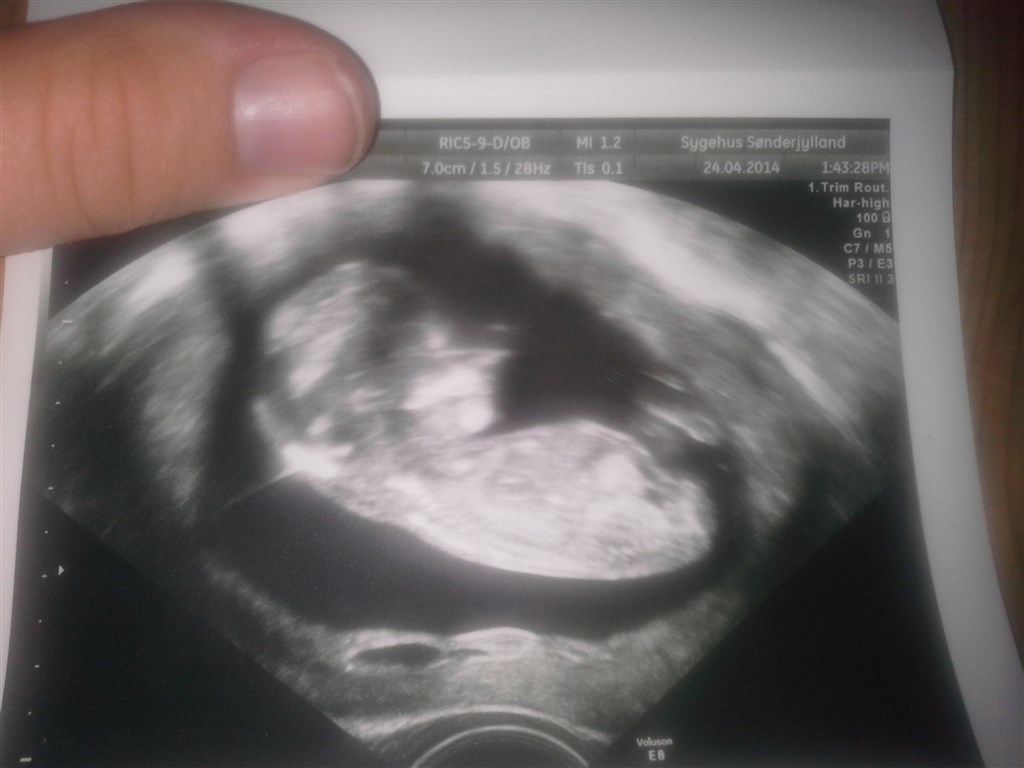

Jeg var til nf i torsdags og er idag 12+5 og er lidt i tvivl om jeg virkelig kan se kønnet på det her billede?

Det kan du under ingen omstændigheder. Begge køn har i øvrigt en tap på dette stadie.

Jeg vil sige nej

Nogle snakker om tappens retning, altså om den peger op eller ned, men det passede ikke på vores piges nf-billede - så skulle hun havde været en dreng. Så det er ikke altid til at regne med

Nej, tor jeg ikke du kan. Da jeg var til kønsscanning var det billeder der viser baby som sad den på en kopimaskine, der viste kønnet, så du må nok vente lidt endnu :-)